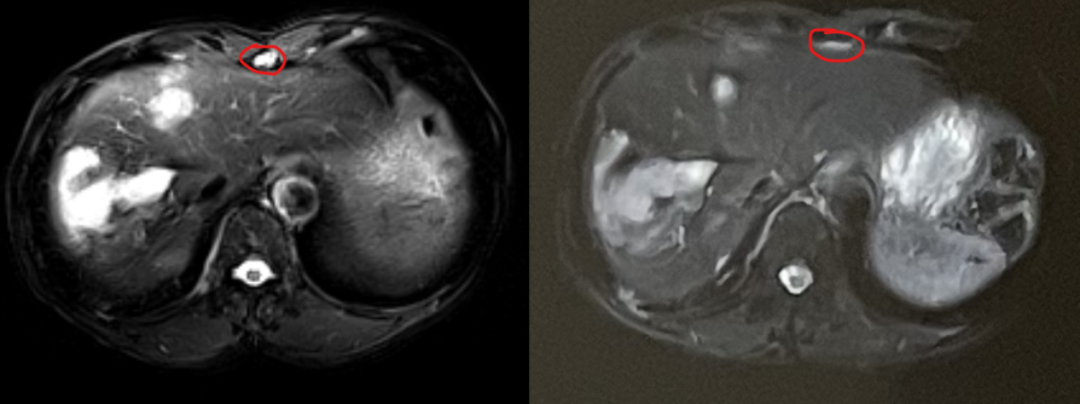

After exhausting conventional options, the family learned about heavy ion therapy’s efficacy in pancreatic cancer through patient communities. They consulted Dr. Chen Weizuo of Wuwei Heavy Ion Center (home to China’s first domestically developed heavy ion therapy system). Following a multidisciplinary expert panel review, Deputy Director Zhang Yanshan explained: "While Mr. Pu has developed resistance to first-line therapies, his high CPS expression suggests carbon ion therapy could enhance local tumor control and reshape the immune microenvironment, potentially re-sensitizing him to immunotherapy." Mr. Pu’s family chose to pursue treatment despite challenges. Over 15 sessions (60 Gy (RBE)/15 fractions for the liver, 58.5 Gy (RBE)/14 fractions for the pancreas), he experienced minimal side effects. Post-treatment, his CA19-9 dropped to 9,450 U/ml. A follow-up in February 2025 revealed further decline to 1,975 U/ml, with significant tumor shrinkage. Encouragingly, he qualified for a clinical trial targeting the KRAS G12D mutation, reigniting his fight.

(Imaging shown: Tumor regression post-carbon ion radiotherapy, left pre-treatment, right 1-month post-treatment.)